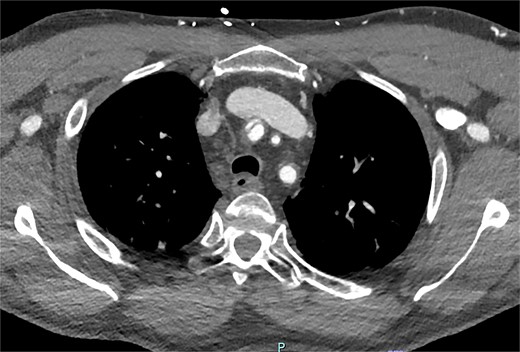

On arrive to the emergency department, the patient was found to be hypertensive with a blood pressure of 220/120 mmHg. Physical examination of the patient revealed no significant clinical findings. Serial troponins with corresponding ECG’s were undertaken which demonstrated no new evidence of myocardial ischaemia. Based upon the patient’s symptomatology, he underwent a CT aortogram which demonstrated a dissection arising from the proximal brachiocephalic artery. No dissection was noted in the ascending aorta, and there was no evidence of the brachiocephalic artery dissection extending into the subclavian or carotid arteries (Figs 1–3).

Axial slice from CT aortogram demonstrating the proximal aspect of the dissection flap.

Axial slice from CT aortogram in greater detail of the dissection flap.